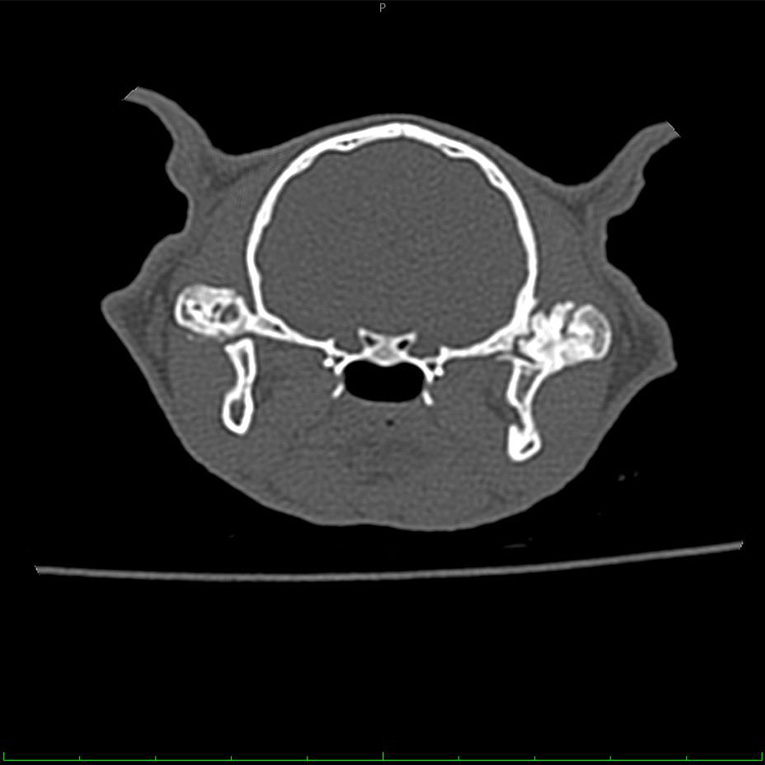

ფისოს ჩაუტარდა კომპიუტერული ტომოგრაფია კახა ბენდუქიძის კამპუსში მდებარე კომპიუტერული ტომოგრაფიის ცენტრში Vet CT • ვეტ სითი-ში. კვლევის შედეგად დადგინდა ორივე საფეთქელ-ქვედა ყბის სახსრის ანკილოზი. ანკილოზი არის მდგომარეობა, როდესაც სახსარში მოძრაობა შეუძლებელია ძვლების სასახსრე ზედაპირების შეზრდის გამო.

პოსტს თან ერთვის კომპიუტერული ტომოგრაფიით მიღებული გამოსახულება.